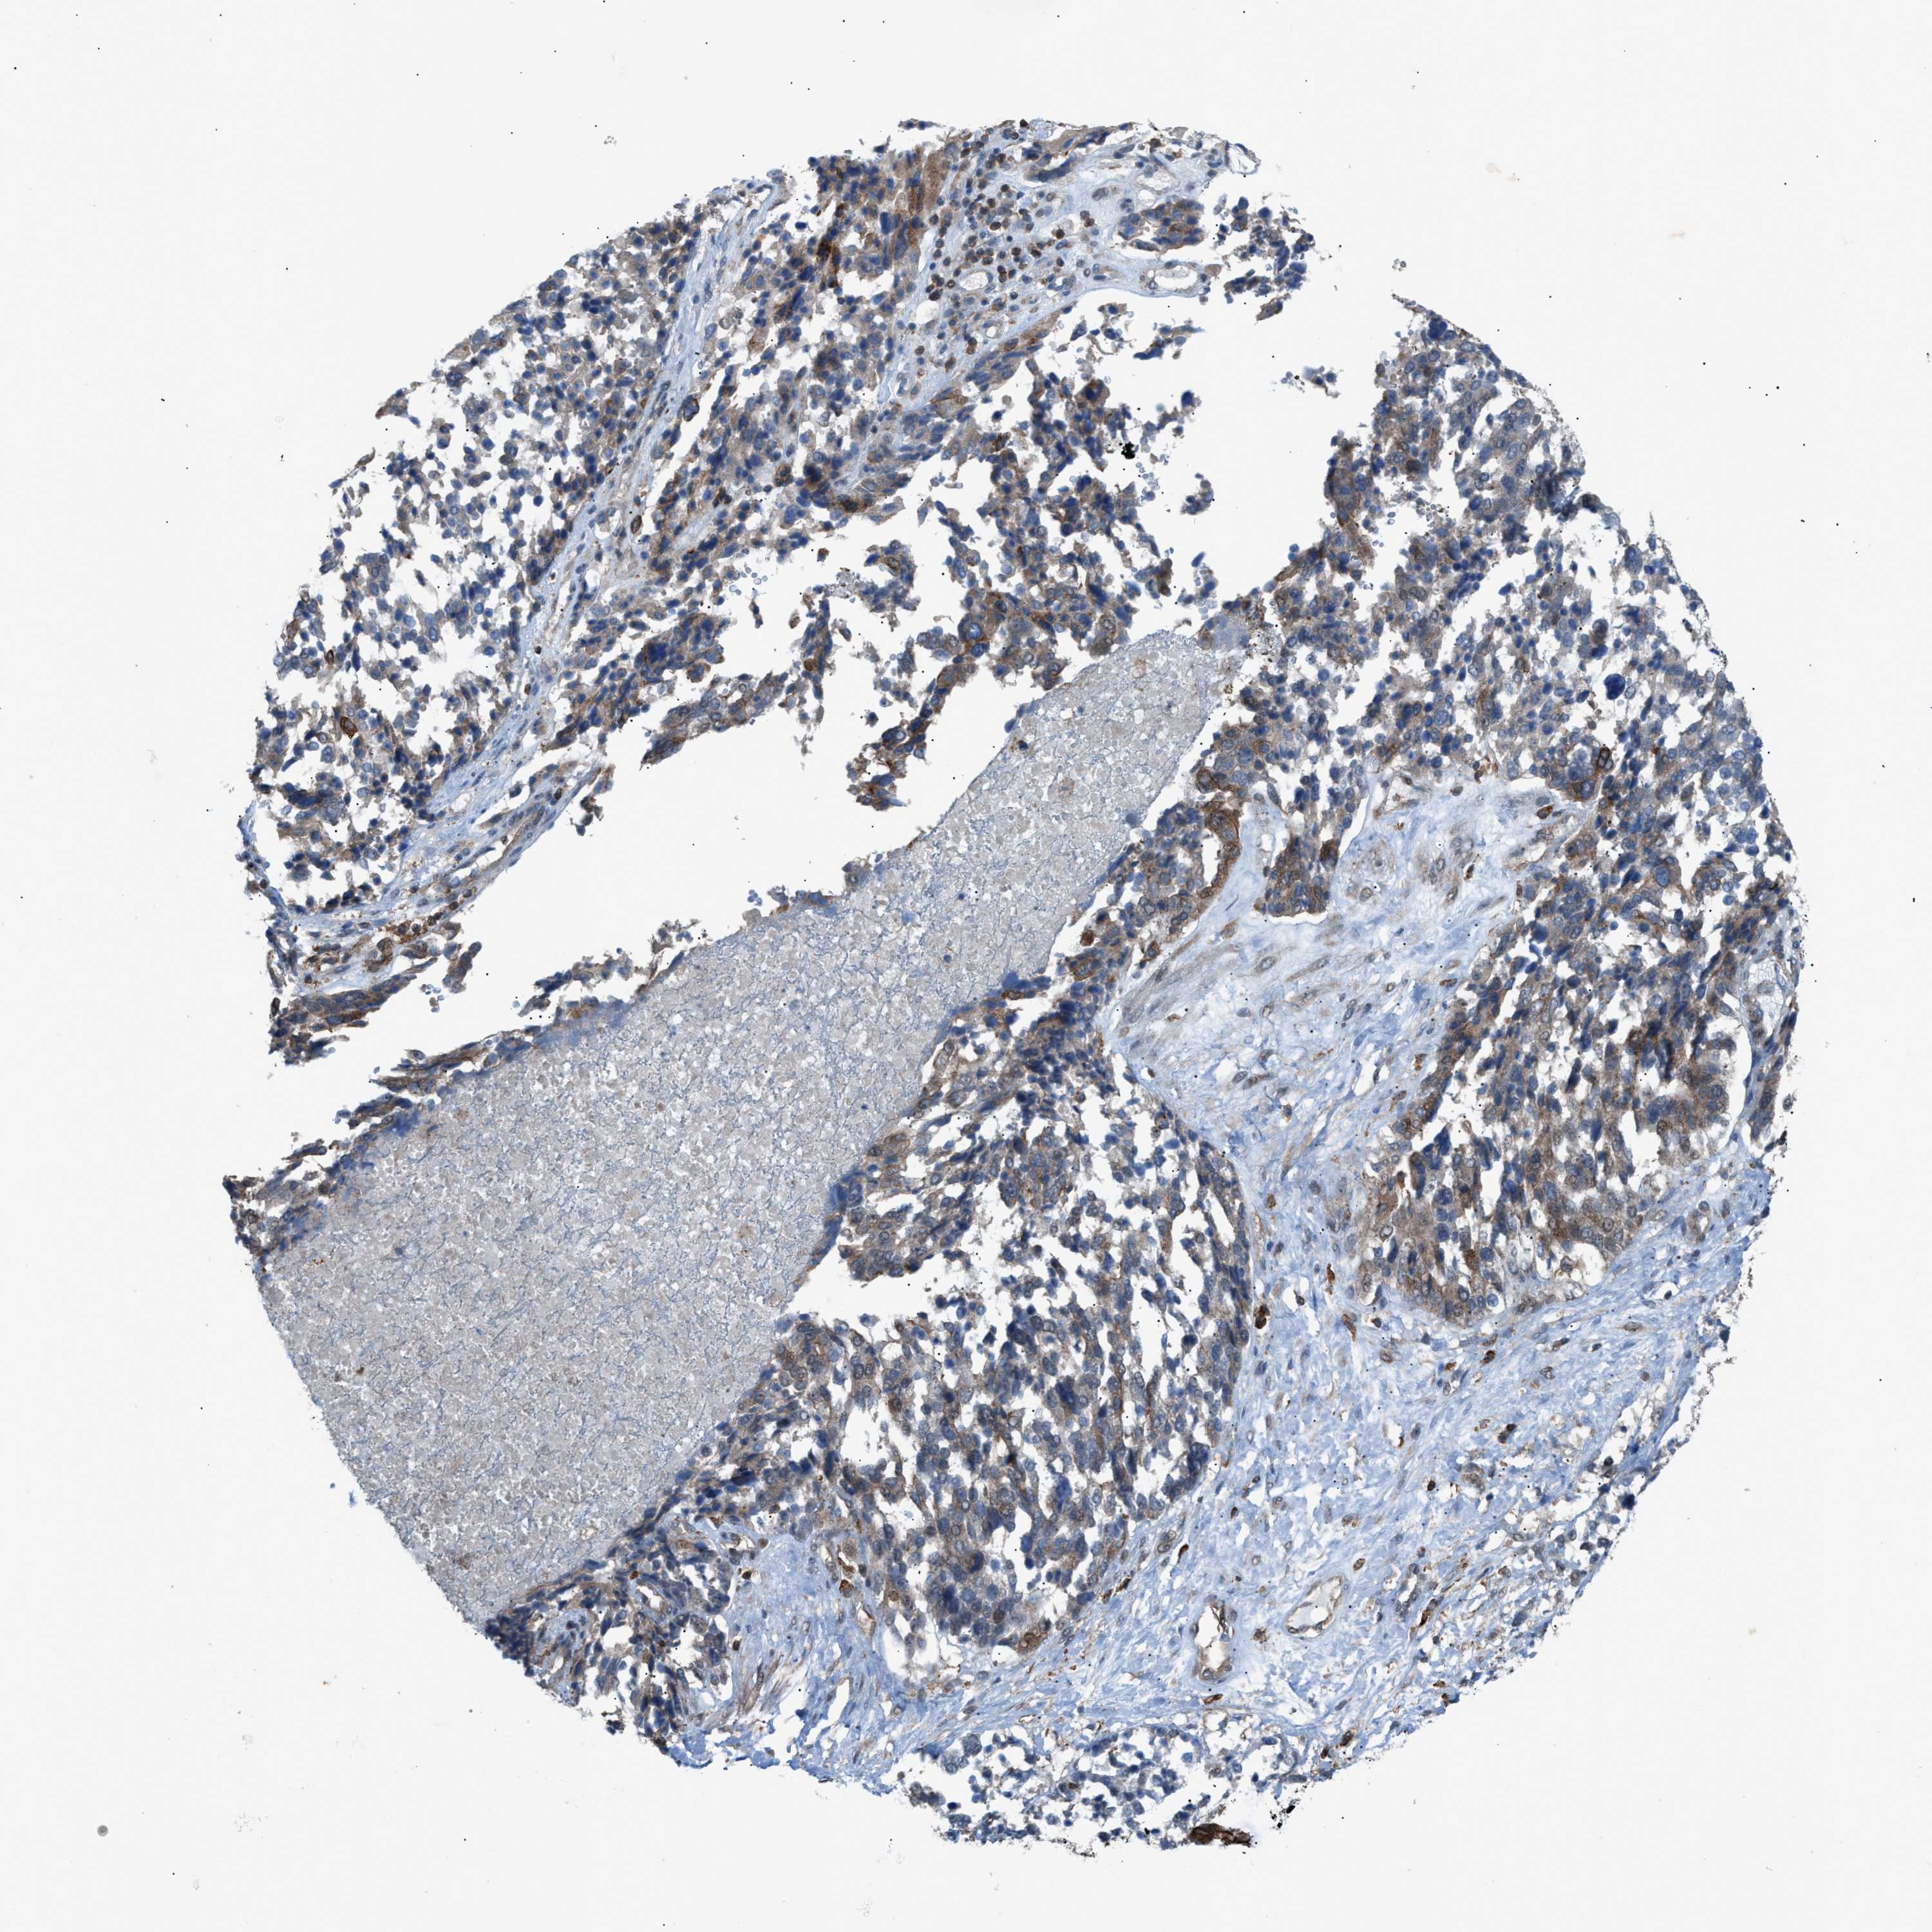

OVARIAN CANCER - Protein expressioni

A mouse-over function shows sample information and annotation data. Click on an image to view it in a full screen mode. Samples can be filtered based on level of antibody staining by selecting one or several of the following categories: high, medium, low and not detected. The assay and annotation is described here.

Note that samples used for immunohistochemistry by the Human Protein Atlas do not correspond to samples in the TCGA dataset.

Antibody stainingi

Antibody staining in the annotated cell types in the current human tissue is reported as not detected, low, medium, or high, based on conventional immunohistochemistry profiling in selected tissues. This score is based on the combination of the staining intensity and fraction of stained cells.

Each image is clickable and will lead to virtual microscopy that enables deeper exploration of all samples and also displays staining intensity scores, fraction scores and subcellular localization as well as patient and tissue information for each sample.

Antibody HPA015323

Antibody HPA015810

Carcinoma, NOS